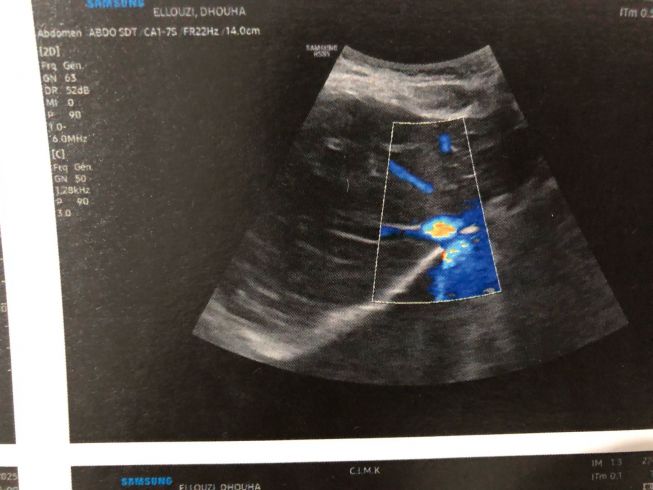

أنا طالبة عمري 21 سنة، أُعاني منذ فترة من حصاة في الحالب حجمها حوالي 6 ملم، مسببة لي آلامًا شديدة وتسببت حسب نتيجة السكانير في توسّع كبير في مجاري البول والكلية.

الطبيب أكّد أن وضعي يحتاج إلى وحتى كيف استعملت الدواء ماحبتش تتداوى  تحاليل وأدوية عاجلة، وبنسبة كبيرة تدخّل جراحي لتفادي أي مضاعفات خطيرة لا قدّر الله.